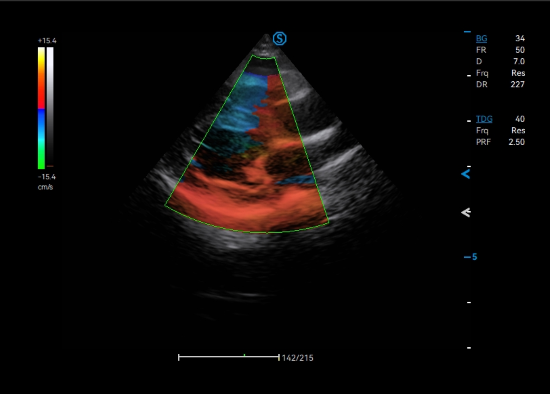

For Cardiac Assessment

Adaptive TDI assesses muscle wall characteristics throughout the cardiac cycle with consistent measurement via self-adaptive tracing technology.

Color M & AMM are specialized for detecting subtle changes, monitoring during surgery, and assessing cardiovascular function and injury severity.

Triplex integrates anatomical imaging, dynamic flow observation and spectral analysis for a comprehensive assessment on vascular disease from multiple perspectives. PW auto correlation being activated during triplex on is to help present another real time quantitative analysis.